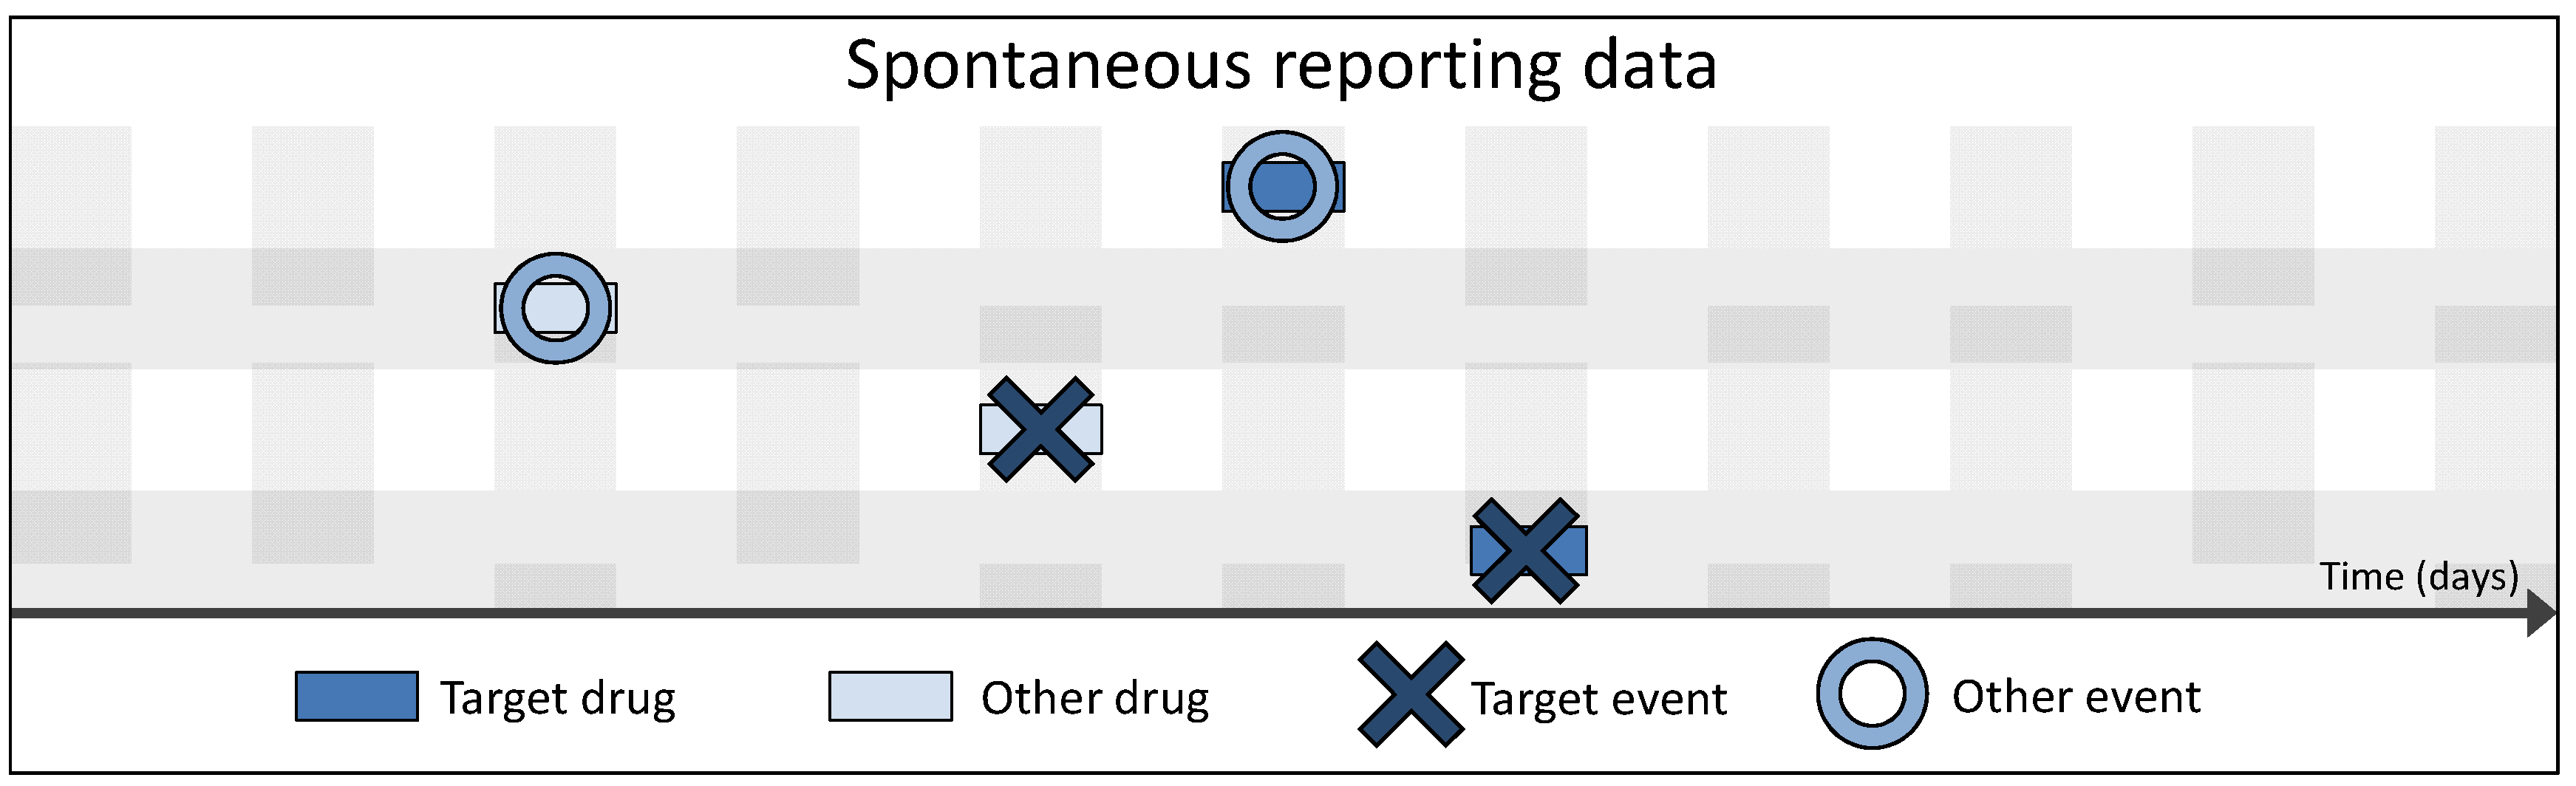

3.2. Spontaneous vs. Longitudinal Data